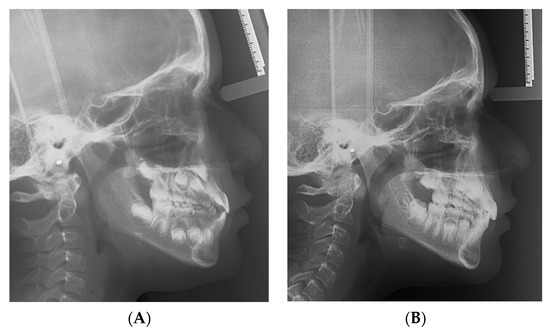

| Variables | Normal Values | Pretreatment | Posttreatment |

|---|---|---|---|

| Angular degrees | |||

| SNA | 82 | 87.7 | 89.6 |

| SNB | 80 | 85.3 | 83.5 |

| ANB | 2 | 2.5 | 6.2 |

| SN to Palatal Plane | 8 | 9.6 | 9.6 |

| SN to Mand. Plane | 32 | 33.3 | 33.5 |

| Co-Go-Me | 125 | 136.1 | 130 |

| Upper Inc. to Palatal Pl | 110 | 119 | 113.6 |

| Lower Inc. to Mand. Pl. | 90 | 87.5 | 91.8 |

| Linear, mm | |||

| Wits | 0 | −6.3 | −3.1 |

| Overjet | 2.5 | 0.4 | 2.7 |

| Overbite | 2.5 | 1.1 | 3.6 |